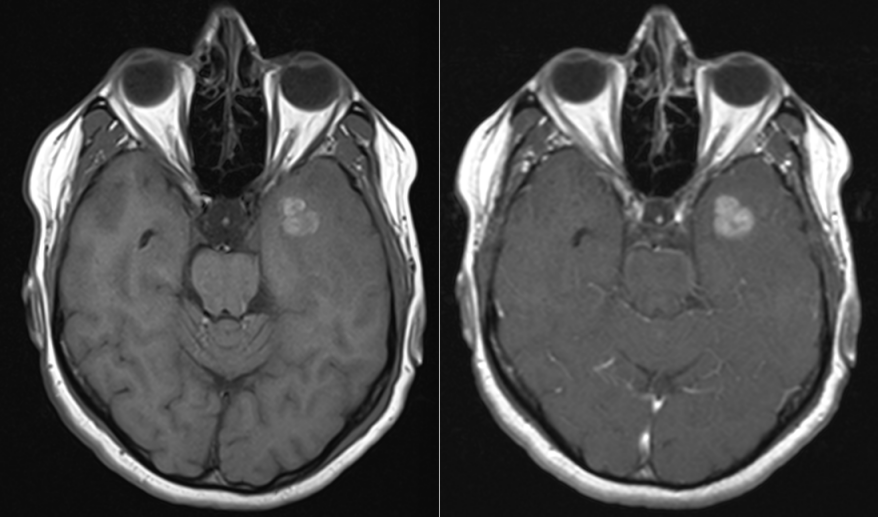

- Imagistică cerebrală: RMN-ul cu substanță de contrast este metoda de elecție, dar și CT-ul poate fi util.

Celulele canceroase se desprind din tumora primară, pătrund în vasele de sânge și călătoresc spre creier. Acolo, ele trec de bariera hemato-encefalică – o structură protectoare care apără creierul de substanțe toxice – și încep să se multiplice. De cele mai multe ori, metastazele apar în zona joncțiunii dintre substanța albă și cea cenușie, unde fluxul sanguin este bogat și viteza de circulație este mai redusă.

Metastazele cerebrale apar frecvent în emisferele cerebrale (80%), mai rar la nivelul cerebelului (15%) sau trunchiului cerebral (5%). Localizarea influențează simptomele și posibilitățile de tratament.

- În mod particular metastazele chistice se pretează la intervenție chirurgicală, având un răspuns slab la radioterapie per primam.